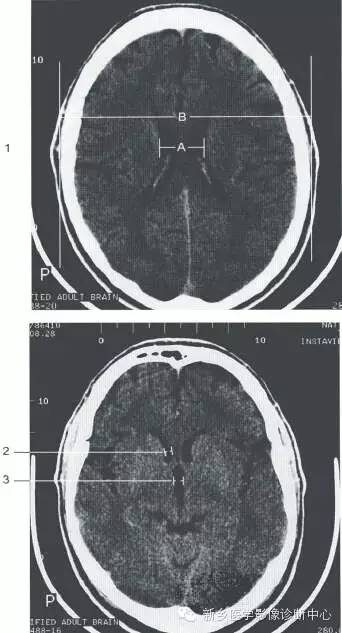

颅脑大体及磁共振断层解剖